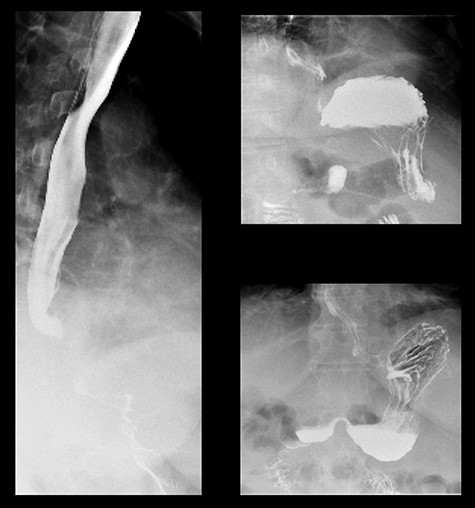

A 59-year-old female presented to the emergency department with a 2-week history of progressive central abdominal pain and distention on a background history of a laparoscopic adjustable band insertion 11 years previously. She had associated nausea, vomiting and denied dysphagia, odynophagia, or change in bowel habit. Clinically, she was afebrile, tachycardic, and on examination, displayed diffuse abdominal tenderness and guarding. Inflammatory markers were mildly elevated (white cell count 13.7 × 109/L, C-reactive protein 105 mg/L), and a moderate hyperlactatemia was observed (lactate 2.4 mmol/L). A plain film abdomen demonstrated a distended, air-filled stomach (Fig. 1). Subsequent computed tomography of the abdomen and pelvis demonstrated an intragastric band erosion with the internalization of the entire gastric band and distal connector tubing within the gastric lumen (Fig. 2). Moderate free fluid and ascites were noted with considerable mesenteric inflammatory fat stranding. The portal vein was non-opacified, indicating a possible portal vein thrombosis (PVT).

The patient was promptly brought to the theater for an exploratory laparotomy. Approximately 30 cm of ischemic small bowel segment with engorged mesentery was identified and resected; while doing so, blood clots were extruding out of the mesenteric vascular arcade. An on-table OGD was performed, demonstrating a deformed shaped stomach. The gastric band had completely eroded through the wall of the stomach. A biofilm had formed around the band device from the distal connecting tubing, tracking into the fundus of the stomach and sealing the perforation (Fig. 3). The biofilm was tracked to the stomach externally, the stomach opened and the device retrieved (Fig. 4). The stomach was closed in two layers and abdominal drains were inserted prior to closure.